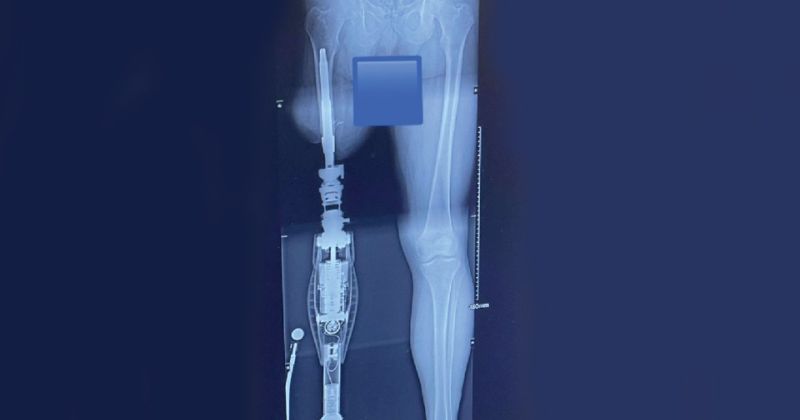

With an amputee-centered approach, Quebec-based Ethnocare has innovated a prosthetic solution to manage residual limb volume fluctuation for better comfort, stability and limb health for lower extremity amputees.